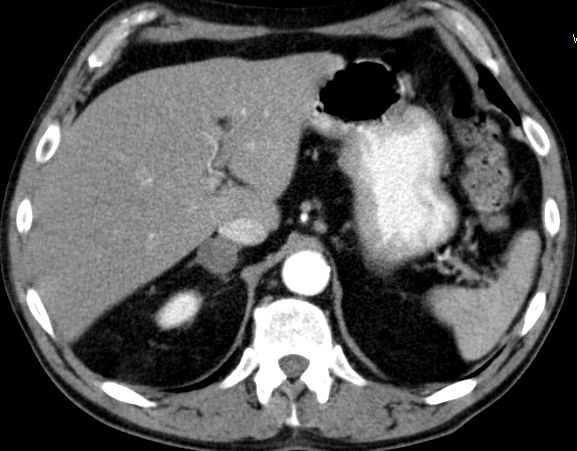

Phaeochromozytom Tumoren des Nebennierenmarks

Nebennieren - Rinden - Tumoren

Staging: ENSAT-Klassifikation

Stadium IStadium II Stadium III Stadium IV

= 5 cm> 5 cm

Diagnostik